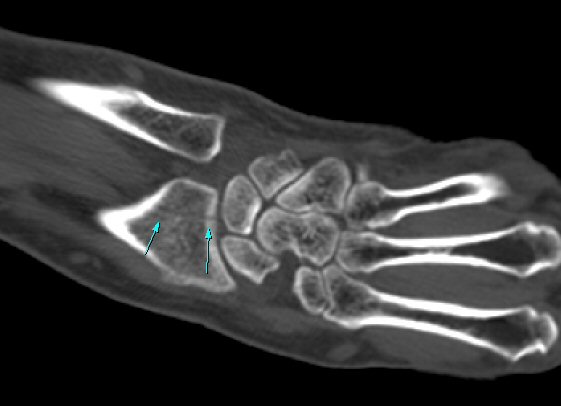

ŽÃÍÀÚ¸¦ ¾à°£ ôÃ÷À¸·Î À̵¿ÇÏ´Ï ¿ä°ñ ¸»´Ü¿¡ ÇÇÁú°ñ ¿¬°á¼º ¼Ò½Ç(loss of cotical continuity)ÀÌ °üÂûµÊ(»çÁø 2, 3).

¿ä°ñ Ⱦ´Ü¸é°Ë»ç¿¡¼­ lister's tubercle ̫̿¿¡¼­ ÇÇÁú°ñ ¿¬°á¼º ¼Ò½Ç(loss of cotical continuity)ÀÌ °üÂûµÊ(»çÁø 4).